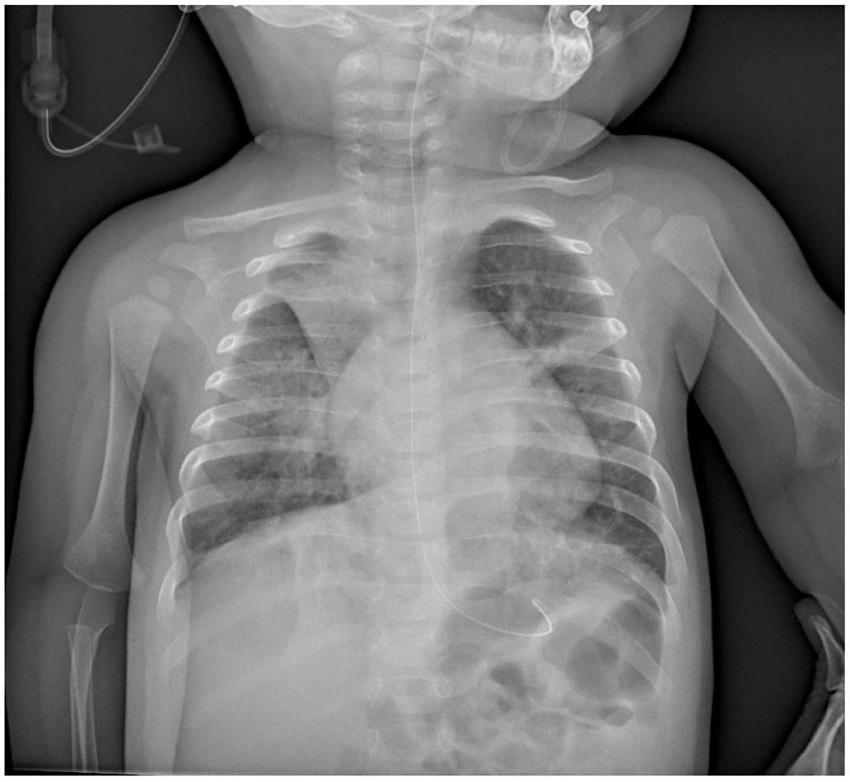

Al quinto día de ingreso hospitalario, se objetivó un empeoramiento clínico, con mala tolerancia oral, vómitos, deposiciones diarreicas, fiebre elevada y desaturaciones, pese a oxígeno a 2 L en gafas nasales. Se hizo una nueva radiografía de control en la que se objetivó una atelectasia del lóbulo superior derecho con persistencia de engrosamientos bilaterales difusos bilaterales (figura 2). Estos nuevos hallazgos se corresponden con un empeoramiento analítico, con elevación del D-dímero, leucocitosis, discreta elevación de la proteína C reactiva e interleucina-6 elevada (leucocitos 13,24 x 103, proteína C reactiva 10,4 mg/L, D-dímero 897 ng/mL, IL-6 14,5 pg/mL).